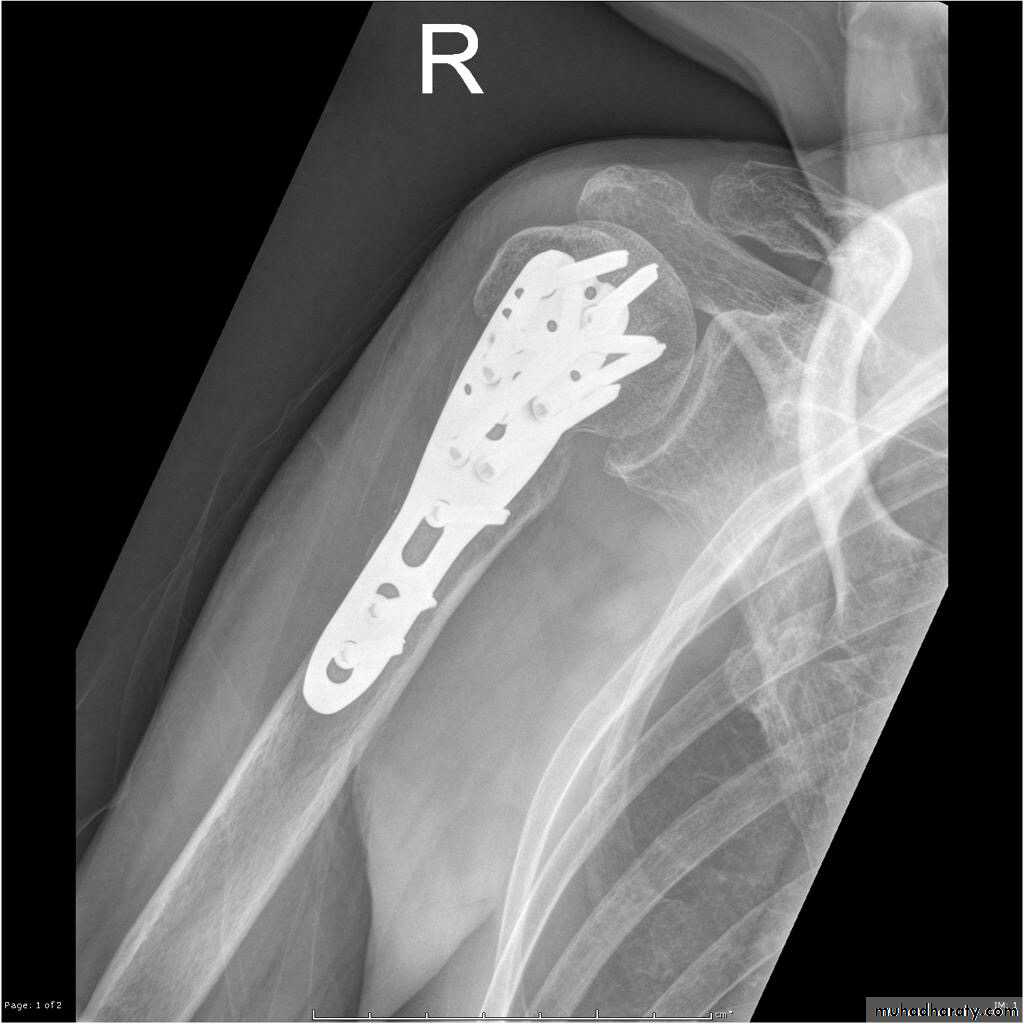

• Close reduction (MUA&sling ) 6weeks and active exercise later if failure

• Open reduction & internal fixation by percutaneous pinning plate and screws or intramedullary nailing21

TREATMENT

22

Plate and screws

23